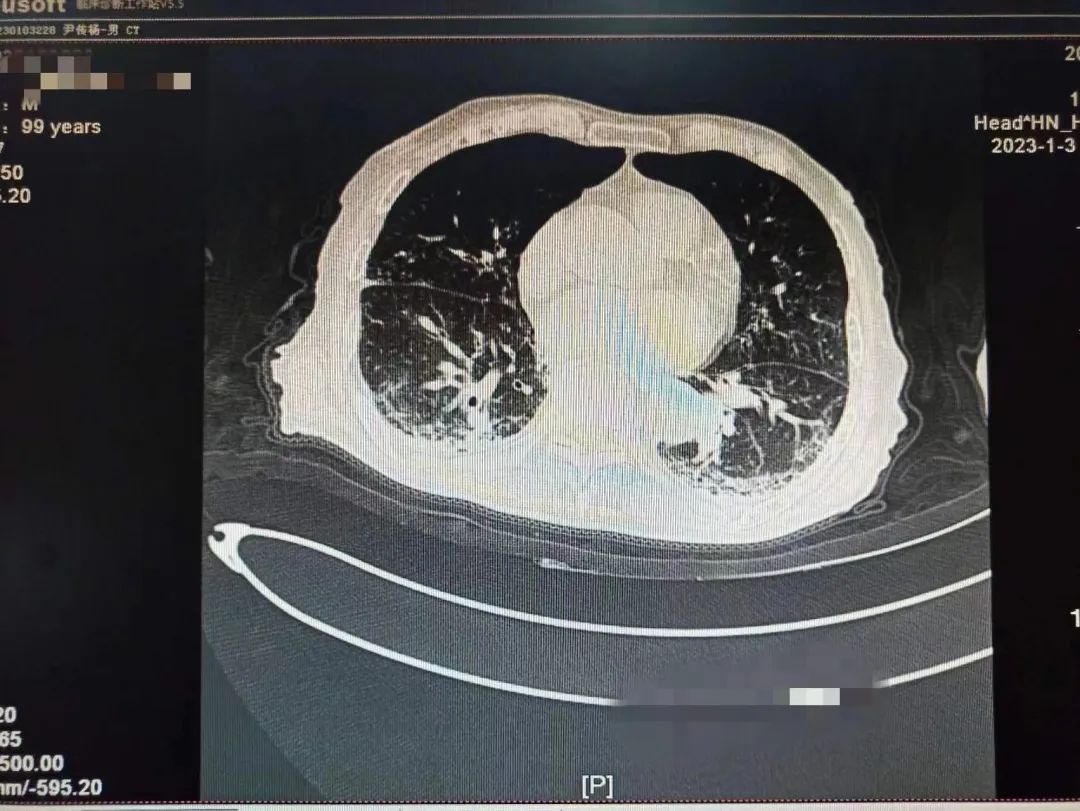

学校一附院呼吸与危重症医学科一名患者刘老爷子还差几天就到100岁生日,该患者从2022年12月22日开始持续发热,咳嗽。一开始只是以为普通的感冒,没特殊注意,后逐渐出现胸闷,乏力,精神差,在当地医院完善肺部CT,两肺大片病毒性肺炎表现,新冠核酸阳性,家属急送一附院就诊。

根据国家卫建委发布《新冠冠状病毒感染诊疗方案》最新版本指南及结合患者个体化诊疗,考虑到老人高龄,有糖尿病基础疾病,血氧饱和度偏低,属于危重症高危人群,专家团队决定给予paxlovid抗病毒治疗,激素、呼吸支持等治疗。患者住院期间一度出现嗜睡,精神极差,刘家昌主任团队时刻关注病情变化,随时调整治疗方案,并多次指出,对于这种重症肺炎患者治疗中,血氧饱和度偏低的情况,俯卧位通气具有非常重要的作用!需要“应趴尽趴”,对血氧饱和度偏低有明显改善作用!

不放弃每一个生命!全力救治!经过连续数日医护团队的精心救治,2023年1月9日,呼吸与危重症医学科医护团队再次对老人病情进行综合评估,检查显示患者肺部病灶明显吸收,精神明显好转,可以正?;疃?,和感染前身体体征一致。出院当天老人握着刘家昌主任的手激动的说:“多亏刘主任了,要不是你和咱们医院医护团队,我这关是闯不过去了,我还以为我过不去这一百岁坎了?!绷跫也魅味岳先撕图沂粝晗附淮顺鲈嚎蹈粗傅家饧白⒁馐孪?。